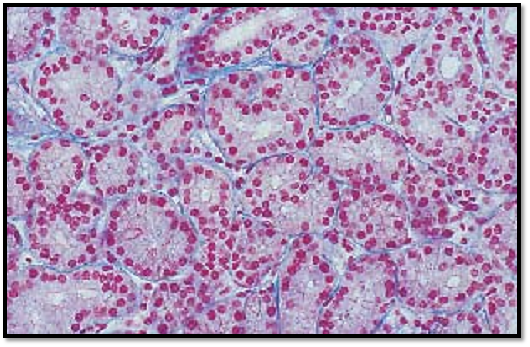

The tubules of the lacrimal gland of ten have wide lumina. They are therefore often referred to as tubuloalveolar glands .The irregularly shaped tubules can be clearly assessed at higher magnification. Note the shape of the gland cells (secretor y cells). The round nuclei are in basal position. The cytoplasm appears light, and cell borders can be clearly recognized in some places. Myoepithelial cells are found between the gland epithelium and the basal membrane. Note the delicate connective tissue between the tubules (here stained blue). The secretory product of the lacrimal glands (tears) moisturizes the cornea and the conjunctiva of the eyeball as well as the eyelids.

Stain: azan; magnification: × 200